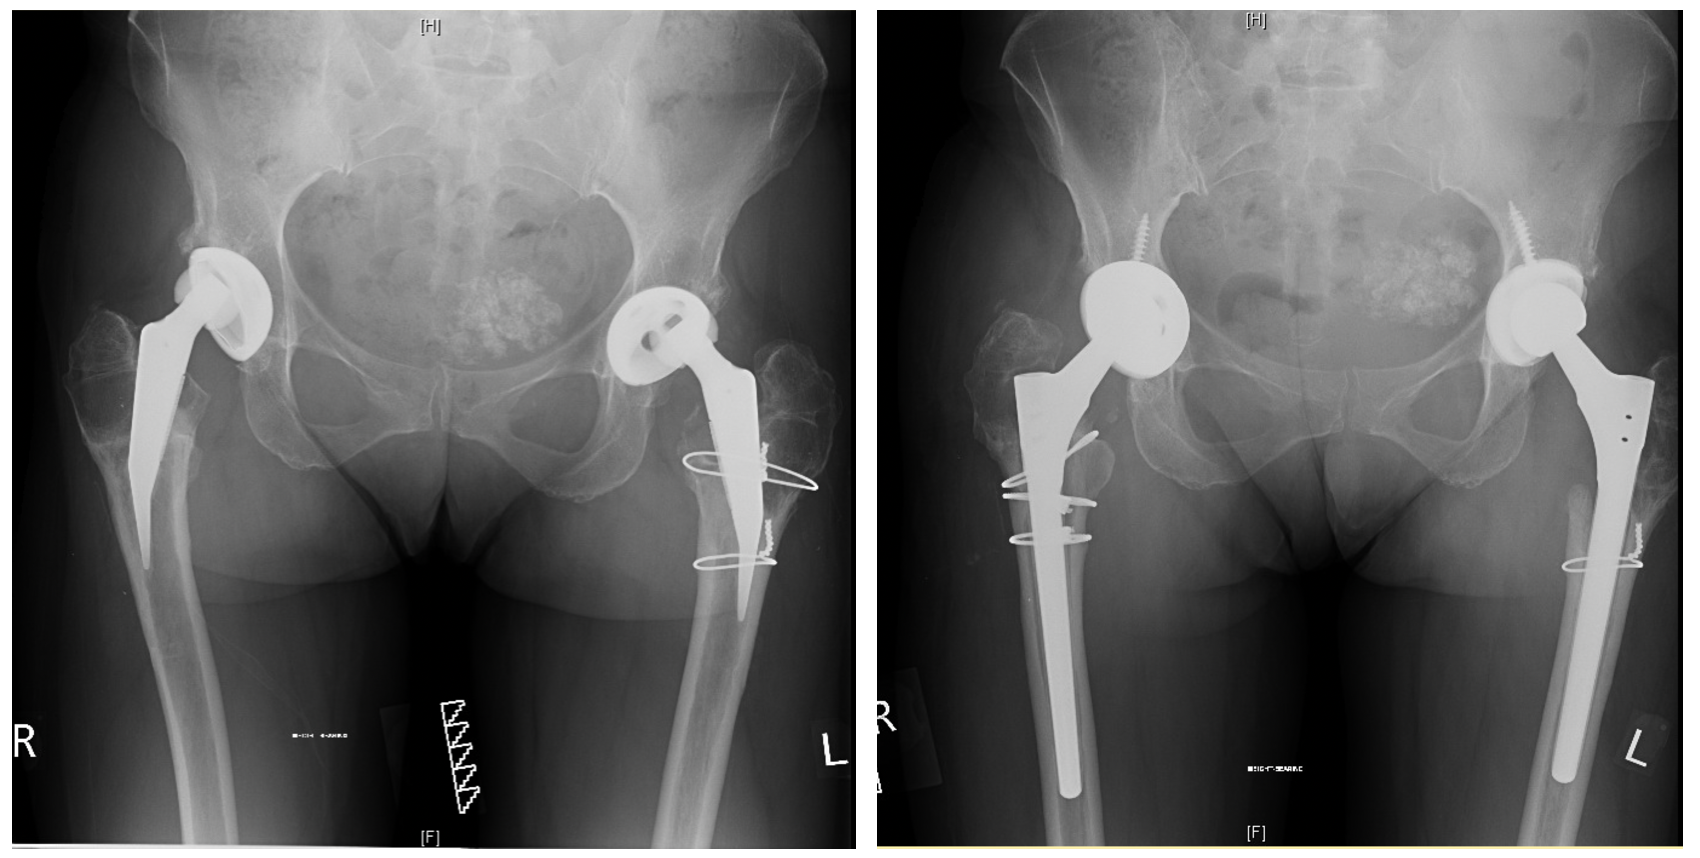

BILATERAL HIP REPLACEMENT

"Getting my life back"

I'm so trilled with my new hips I thought I'd email you to fill you in on what they are doing for me: Climbed a gate with ease about 2 weeks ago, something I haven't been able to do for a few years. Did a 16km canal walk last week with ease and even better no grumbling legs/joints afterwards

TOTAL HIP REPLACEMENT

"Incredible experience improving my life"

Mr. Vioreanu is an incredible surgeon who significantly improved my mobility and quality of life in just 2 days after hip replacement surgery!

"Thoroughly Professional Care"

I had my hip replaced with Mr. Vioreanu last year. I was suffering for years with my hip but it was only afterwards I realised how much pain and discomfort I was living with. From the first time I met Mihai I felt comfortable with the man who eventually would be operating on me. He explains things in a manner that even a novice like myself can understand.

"Walking poles only two weeks after surgery - I am so happy"

As a woman in her sixties, who has always been active, I was delighted to be introduced to Mr Vioreanu. A friend had recommended me to him as her GP was impressed with her rapid recovery. At the consultation the information was clear and I was given a very informative booklet to take away and study. I was admitted on a Tuesday morning, operated on Tuesday afternoon and home on Thursday evening.

"Very down to earth & Accessible at all times"

I attended the Beacon Hospital for almost nine years and the Hip and Knee Specialist was trying to bring my right knee 'back from the brink' with daily pain killers and injections. I decided to go attend Mr. Mihai Vioreanu and I liked him instantly. He told me that my right hip was causing most of my knee problems. I accepted what he said and had a Total Hip Replacement in April 2018. Life has been great since as I no longer take pain killers and I have no pain in my knee.

"Nothing was ever too much bother, whatever the request"

To all the staff at Sports Surgery Clinic. Just 6 weeks ago I received a hip replacement at your clinic and would like to take a few moments to express my sincere gratitude for the care and attention I received during my stay. From the very first moment of making contact with the clinic through a telephone enquiry, to the stages that followed - the first consultation, checking in, my pre op consultation, until my discharge 3 days later;

"A New lease of Life totally pain free"

I would just like to thank Mr Vioreanu for the fantastic work which he performed on my hip which was really badly deteriorated and I was in agonising pain and discomfort to the point of struggling to walk. I attended his clinic and had a diagnosis and scan immediately, and successful surgery within two weeks.

" My Highest Recommendation "

A perfect schedule, excellent briefing, completely detailed. My recovery post discharge was rapid and I'm extremely grateful for choosing Mr. Mihai Vioreanu as my specialist.

"Dr. Vioreanu went out of his way for me"

Dr Vioreanu really went out of his way for me and after only 2 weeks I was having the surgery. I couldn't  believe how lucky I was. The surgery went very well and I could walk with no pain straight away after the operation.

Bilateral Revision Hip Replacement

" I can't express this clearly enough: you've come to the right surgeon! "

In my many decades' experience with hip operations Mihai Vioreanu has stood out for two reasons: the exceptional skill he brings to his surgeries, and the depth of empathy, humanity and kindness he shows to his patients.